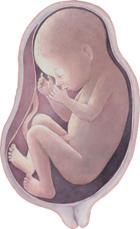

2. Monat: Der Embryo ist so groß wie ein Daumen und sieht schon wie ein winziger Mensch aus.

Der Embryo wächst in der Gebärmutter – die Zeit der Schwangerschaft

3. Monat: Der Embryo ist ca. 8 – 9 cm groß. Gesicht, Arme und Beine sind bereits entwickelt. Man nennt ihn jetzt Fetus.

5. Monat: Die Mutter kann das Strampeln des Fetus wahrnehmen. Auf dem Kopf beginnen Haare zu wachsen.

7. Monat: Der Fetus ist vollständig entwickelt. Er muss nur noch wachsen.

9. Monat: Die Entwicklung des Fetus ist abgeschlossen. Die Geburt kündigt sich durch ein Ziehen in der Gebärmutter (Wehen) an. Die Fruchtblase, in der der Fetus herangewachsen ist, platzt und das Fruchtwasser fließt aus.

Der heranwachsende Embryo oder Fetus ist über die Nabelschnur mit dem Mutterkuchen (der Plazenta) verbunden. So wird er mit allen lebensnotwendigen Nährstoffen und mit Sauerstoff aus dem Blut der Mutter versorgt.

Geburt:

Durch starkes Pressen wird das ca. 50 cm große Baby aus dem Bauch gepresst.